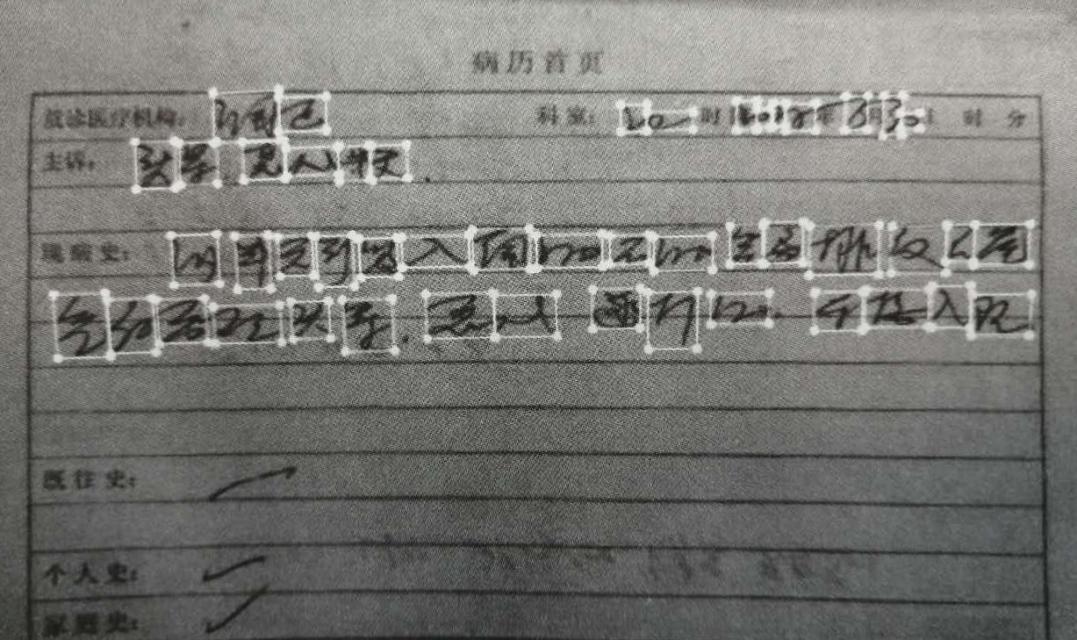

病历文本标注是对病例信息进行文本标框标注,通过对病历内容的文本转录实现电子病历系统建立。如图所示,在一张病历图片中,对病历内容进行文本标注。